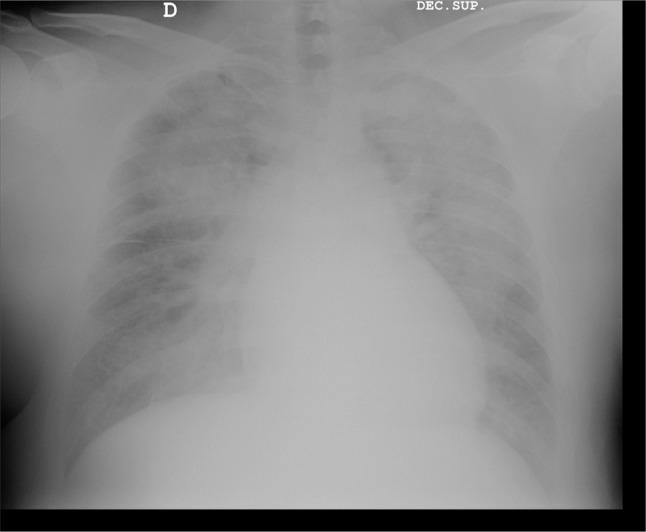

[奥地利综合征:侵袭性肺炎球菌病的一种罕见表现。病例报告及文献综述]

[Austrian syndrome: A rare manifestation of invasive pneumococcal disease. A case report and bibliographic review].

The Austrian syndrome is a pathology caused by disseminated Streptococcus pneumoniae infection and characterized for the triad of pneumonia, endocarditis and meningitis. It has an estimated incidence of 0.9-7.8 cases per ten millions people each year, and a mortality of 32%. Alcohol abuse, as the main risk factor, appears only in four out of ten patients. Moreover, 14% of patientes do not have any risk factor. Two out of three patients are males and it occurs in the middle aged of life. It is more frequently on native valve, aortic valve is injured in the half of the cases. Severe regurgitation occurs in two per three patients. Appropriate antimicrobial treatment and early endocarditis surgery decrease mortality. It is possible that Austrian syndrome epidemiology is changing by the introduction of 13-valent pneumococcal conjugated vaccine in the children´s calendar.

奥地利综合征是一种由播散性肺炎链球菌感染引起的病理状况,其特征为肺炎、心内膜炎和脑膜炎三联征。据估计,其年发病率为每千万人中有0.9 - 7.8例,死亡率为32%。酗酒作为主要危险因素,仅在十分之四的患者中出现。此外,14%的患者没有任何危险因素。三分之二的患者为男性,发病于中年。它更常累及自身瓣膜,半数病例主动脉瓣受损。三分之二的患者出现严重反流。适当的抗菌治疗和早期心内膜炎手术可降低死亡率。由于在儿童免疫程序中引入了13价肺炎球菌结合疫苗,奥地利综合征的流行病学情况可能正在发生变化。